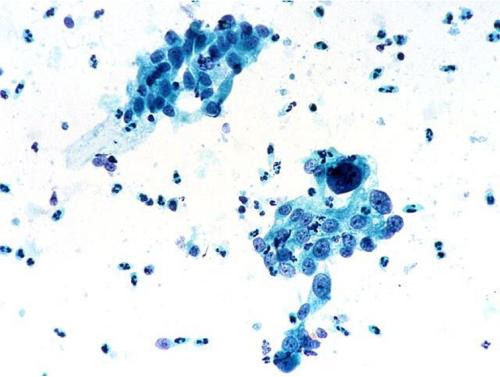

貴陽皮膚細胞重新編程為免疫細胞的樹突狀細胞

日期:2018-12-19 點擊:5120? 瑞典隆德大學的研究團隊首次成功地將小鼠和人類皮膚細胞重新編程為稱為樹突狀細胞的免疫細胞。該過程快速有效,代表了直接重編程誘導免疫的開創性貢獻。重要的是,該發現開辟了開發針對癌癥的新型基于樹突細胞的免疫療法的可能性。 ? ? ? ?樹突狀細胞是免疫系統的哨...